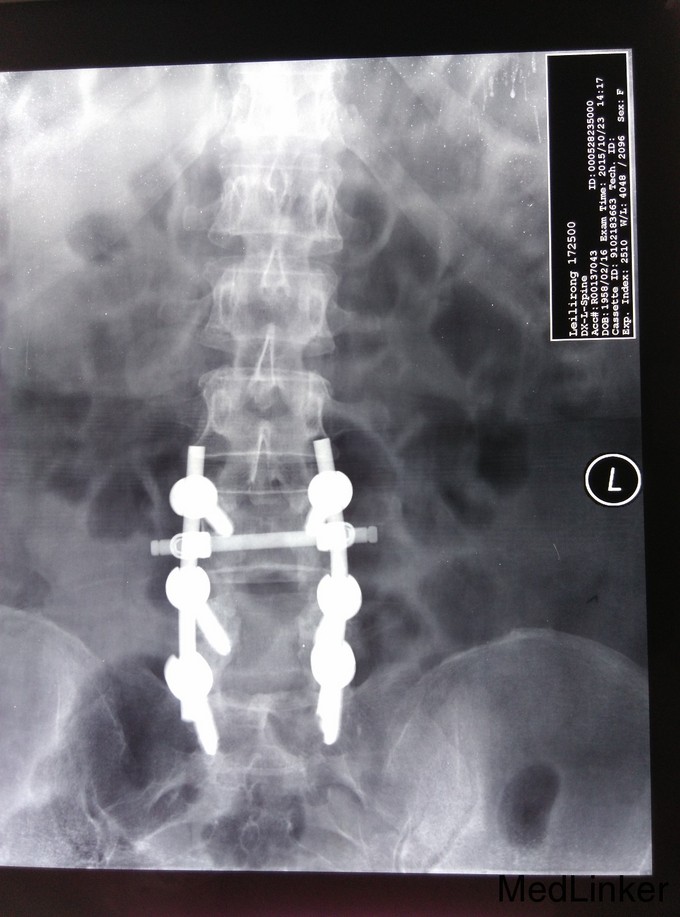

诊断:腰椎管狭窄症、腰椎间盘突出、腰椎骨关节病 治疗:入院后完善相关检查,无明显手术禁忌症,于手术室全麻下行腰4-5、腰5-骶1椎板切除、椎管减压、椎弓根内固定术,

术后给予抗炎、抗感染,消肿、止痛对症治疗,术后第1天拔出引流管,嘱患者腰围保护下地,适度功能锻炼,术后两周拆线,出院,术后患者自诉双下肢麻木大部分缓解,效果良好。